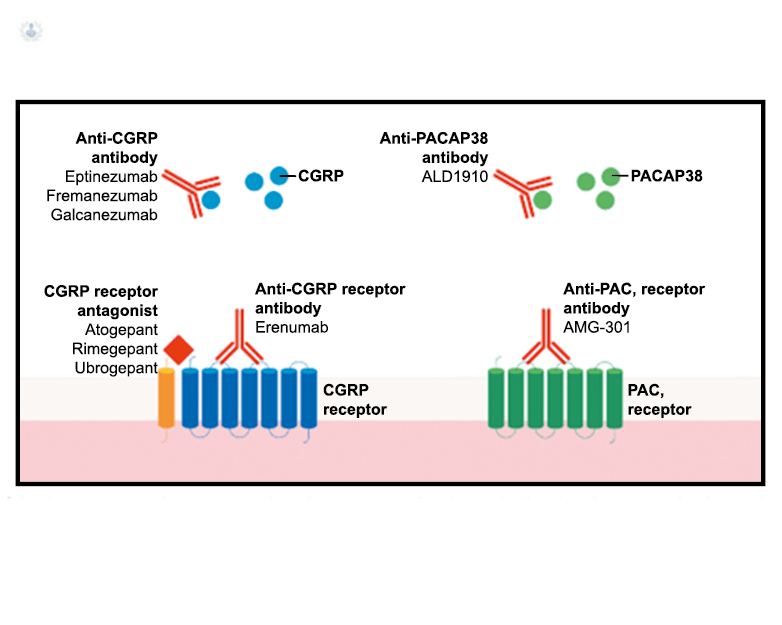

El CGRP es un potente vasodilatador que, cuando se administra a personas que padecen migrañas, se sabe que desencadena ataques(72). Se libera durante los ataques espontáneos(73) o provocados(74), que pueden inhibirse mediante el tratamiento con triptanos(75). Además de sus efectos vasculares, CGRP se ha convertido en un modulador clave de la función neuronal, que tiene efectos importantes en los sistemas de neurotransmisores como el sistema glutamatérgico(76). Sobre la base de los datos clínicos(77), se inició un esfuerzo para desarrollar antagonistas de los receptores de CGRP: los “gepantes”: telgacepant demostró una eficacia mejor que el placebo y comparable a los triptanos(78), como el primer antagonista oral del receptor de CGRP con excelente tolerabilidad a largo plazo(79) y también fue bien tolerado en pacientes que estaban siendo investigados por enfermedad arterial coronaria(80). Sin embargo, el desarrollo de telgacepant se detuvo cuando surgieron problemas con las enzimas hepáticas en un estudio preventivo, que resultó bastante positivo(81). Este efecto no se ha informado con rimagepant(82) Los ditanes, tienen como mecanismo el ser agonistas selectivos del receptor 5-hidroxitriptamina tipo 1F (5-HT1F) en la vía trigeminal, hasta ahora ha demostrado no tener efecto vasoconstrictor asociado. Lasmiditán ha sido hasta la fecha de elaboración de esta revisión la primera molécula aprobada por FDA. (Figura 35)

Los anticuerpos monoclonales contra el péptido CGRP y el receptor (numab y nezumabs) se han desarrollado para capitalizar los efectos antimigrañosos comprobados del bloqueo de los mecanismos CGRP como nuevos tratamientos preventivos. Los anticuerpos contra el péptido CGRP, al CGRP y del receptor CGRP (complejo CLR/RAMP1) han presentado datos positivos de ensayos controlados.(83) (Figura 36 y Tabla 3)

La comprensión de la biología de la migraña a través de una cuidadosa investigación de laboratorio ha llevado al desarrollo de las principales clases de tratamientos: triptanos, agonistas del receptor de serotonina 5-HT1B/1D; gepants, antagonistas del receptor del péptido relacionado con el gen de la calcitonina (CGRP); ditanes, agonistas del receptor 5-HT1F, CGRP anticuerpos monoclonales; moduladores de mGlu5, sin olvidar el efecto ya demostrado por parte de los bloqueantes de los canales de calcio (flunarizina) y de los neuromoduladores; bien se trate de topiramato (Inhibe la acción de la anhidrasa carbónica, bloquea los canales del sodio, aumenta las corrientes de cloro mediadas por GABA, activa las corrientes hiperpolarizantes del K+ e inhibe la activación de receptores a ácido glutámico tipo AMPA), valproato de sodio (Inhibe las enzimas de degradación del GABA y puede aumentar su síntesis, además de tener un papel inhibidor de la transmisión excitatoria de ciertos aminoácidos, entre ellos el glutámico y reducir el umbral de conductancia del calcio y el potasio) y de los antidepresivos de diversas clases como la amitriptilina (antidepresivo tricíclico que impide la recaptación y la inactivación de la noradrenalina y la serotonina en las terminaciones nerviosas) y venlafaxina (inhibe principalmente la recaptación de serotonina y en menor grado de noradrenalina, en la membrana presináptica neuronal, potenciando la neurotransmisión a nivel del sistema nervioso central). El propanolol tiene un efecto antagonista de los adrenoceptores β1 en las neuronas del núcleo VPM (postero medial ventral) del tálamo que responden a la entrada nociceptiva trigeminovascular. Se ha demostrado que el propanolol previene los cambios en el comportamiento y el flujo sanguíneo cerebral inducido por la depresión cortical propagada, además de bloquear los canales de sodio del cerebro(103), modulación del sistema catecolaminérgico central(104) probablemente a través de receptores β-adrenérgicos centrales e interacción cruzada con receptores de serotonina(105) (Figura 4).